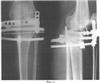

Способ проиллюстрирован сделанными в процессе лечения рентгенограммами нижней левой конечности (в разогнутом состоянии) больной М.:

Фиг.4 – после операции и наложения аппарата внешней фиксации;

В СарНИИТО 13.12.05 было проведено оперативное вмешательство по запланированной схеме (фиг.5). Произвели дугообразный разрез по передневнутренней поверхности проксимального отдела левой голени длиной 12 см. В верхней трети левой большеберцовой кости выполнена корригирующая многоплоскостная остеотомия с формированием внесуставно костно-хрящевого суставного фрагмента. На задней поверхности голени вырезали клин углом в 10° и шириной 8 мм. Затем была пересечена в средней трети малоберцовая кость. Проведенными в сагиттальной плоскости П-образно изогнутой спицей Киршнера и стержнем костно-хрящевой фрагмент зафиксирован в аксиальной плоскости. Интраоперационно под рентгеноконтролем на голень наложен двухсекционный спице-стержневой аппарат внешней фиксации (фиг.4). Спица и стержень закреплены на верхней базовой опоре аппарата посредством тяговых устройств.